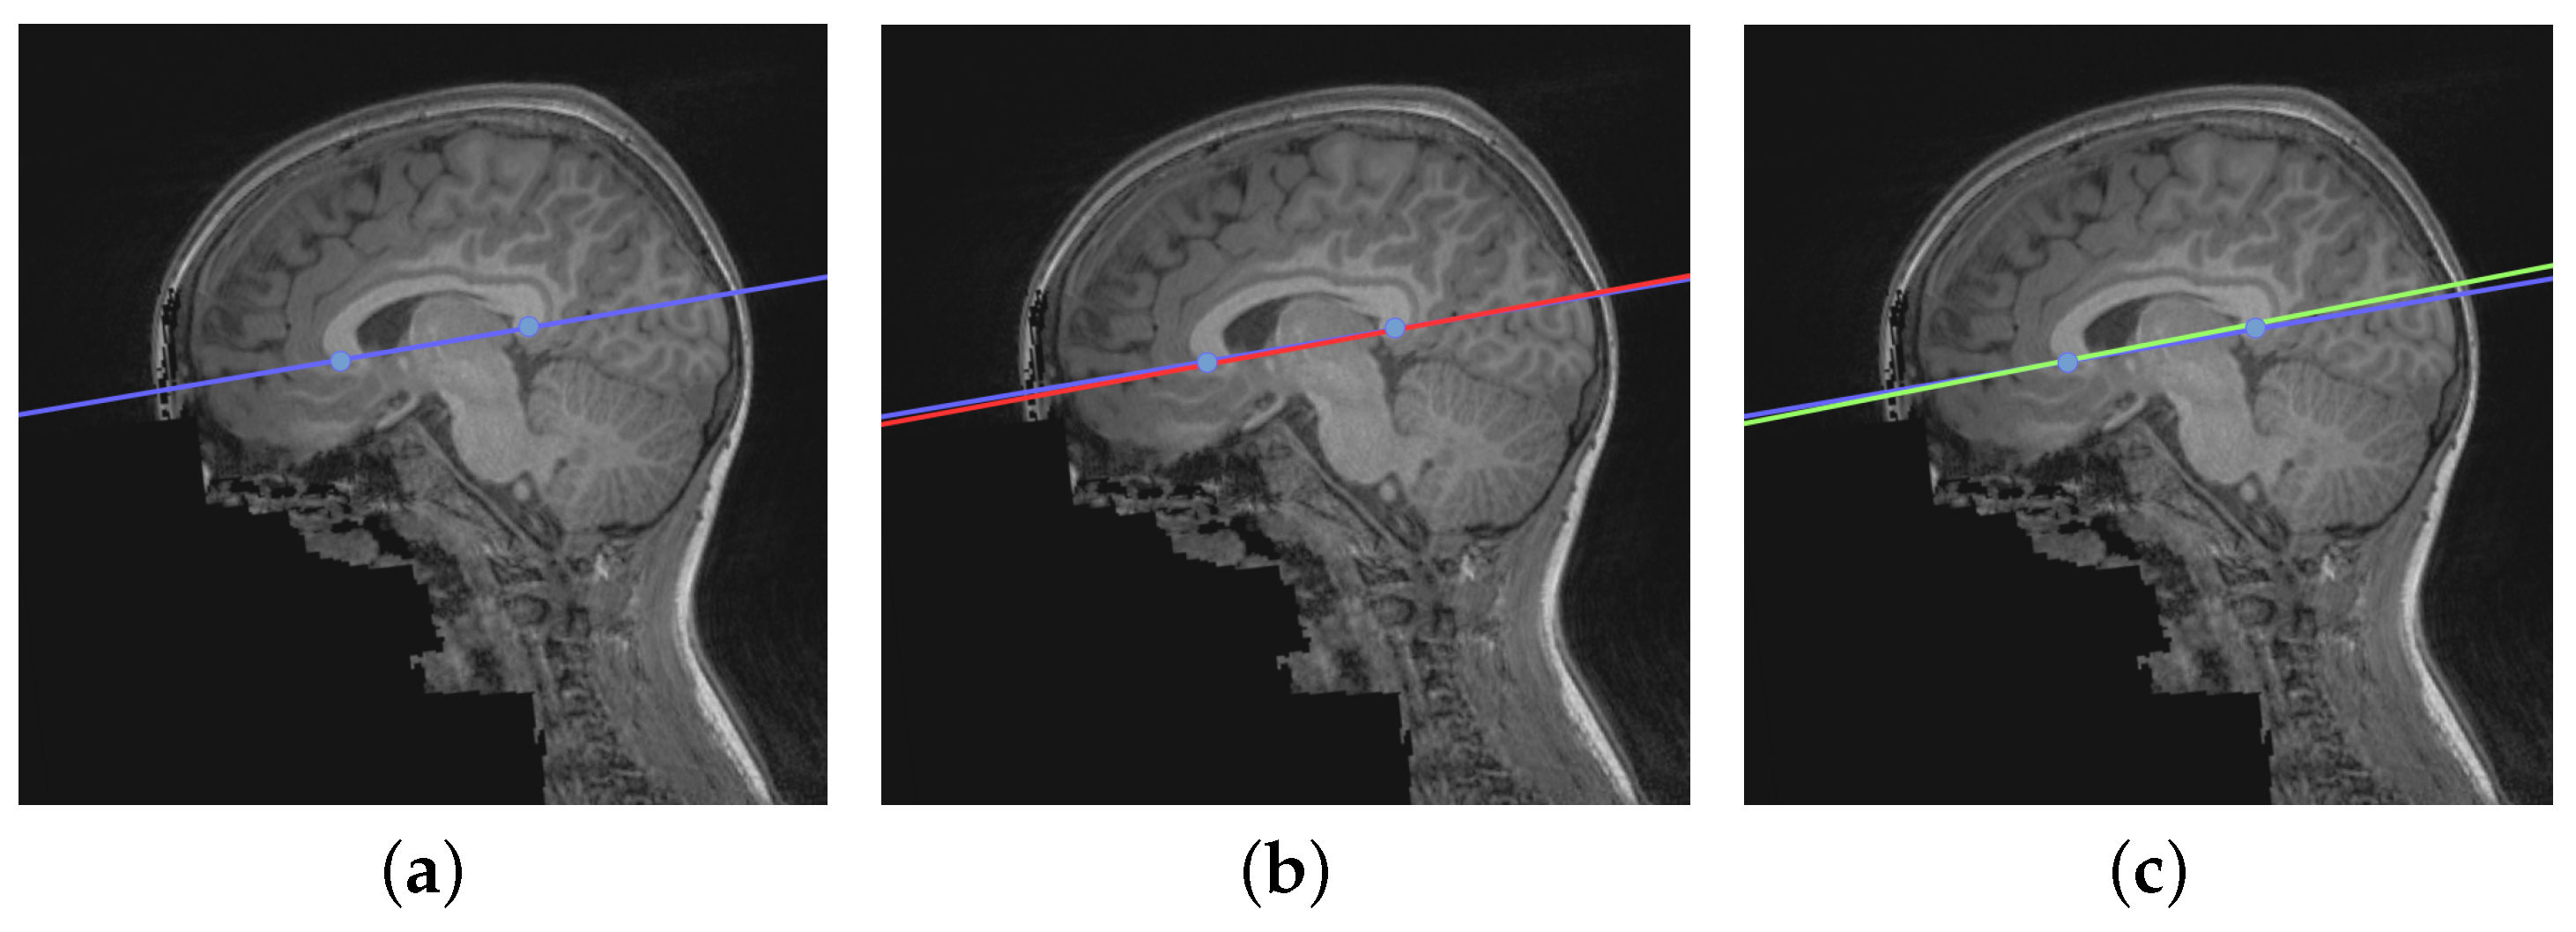

As an example, Figure 8 illustrates the final line detection using both methods. In (a), blue points and line identify the cutting plane indicated by the specialist. In (b), red line identifies the cutting plane automatically generated by the YOLO-based method. In (c), green line identifies the cutting plane automatically generated by the SIFT-based method.

Figure 8. Example case of line adjustment by specialist and automated methods based on SIFT and YOLO models. (a) Blue points and line identify the cutting plane indicated by the specialist. (b) Red line identifies the cutting plane automatically generated by the YOLO-based method. (c) Green line identifies the cutting plane automatically generated by the SIFT-based method.